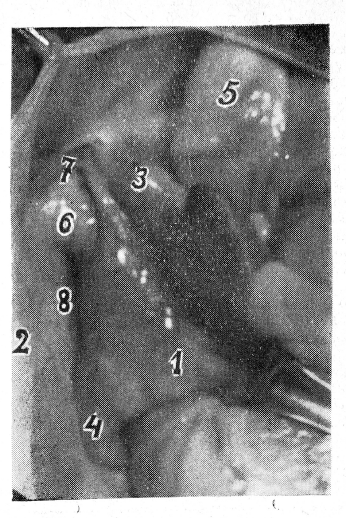

Правый сердечно-перикардиальный промежуток (кавакавальный) возникает, когда сердце отведено влево. Угол между правым предсердием и перикардом составляет при этом 70—75°. Длина промежутка 5—7 см, ширина 1,3—1,5 см. Слева промежуток ограничен правым предсердием, справа — боковой стенкой перикарда, сверху и снизу— конечными отделами верхней и нижней полых вен (рис. 1). В этом промежутке располагается, как правило, одна выпуклость .и два углубления (перикардиальные карманы). В верхнем отделе промежутка под основанием верхней полой вены располагается верхний перикардиальный карман, имеющий вид овального углубления. Диоптрографические данные показали, что углубление соответствует положению дистальной части (перикардиального отдела) правой легочной артерии, а последняя на этом участке покрывает нижний отдел правого главного бронха. Ниже верхнего перикардиального кармана располагается в поперечном направлении (рис. 1) выпуклость цилиндрической формы. Это контурирует сквозь задний листок перикарда верхняя правая легочная вена, а ее положение соответствует дистальному концу правого главного бронха, где он начинает делиться на долевые бронхи. Нижняя правая легочная вена расположена относительно верхней под углом и глубже и, как правило, контура на задней стенке не образует. Ниже контура верхней правой легочной вены расположено второе углубление — нижний перикардиальный карман. Он соответствует промежуточному бронху.

Рис. 1. Правый сердечно-перикардиальный промежуток (кава-кавальный):

1 — правое предсердие; 2 — боковая стенка перикарда; 3 —верхняя полая вена. 4 — нижняя полая вена; 5 — восходящая аорта; 6 — кон; тур правой верхней легочной вены; 7 — верхний перикардиальный карман; 8 — нижний перикардиальный карман.